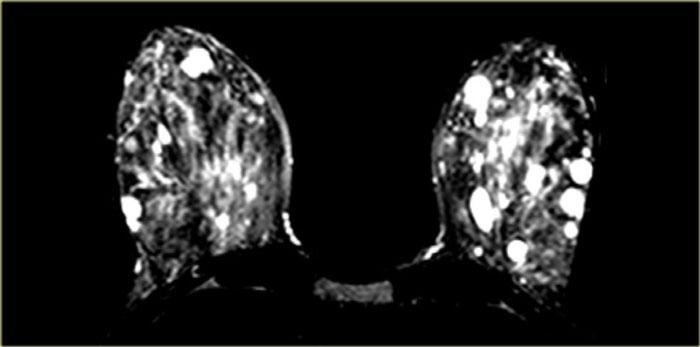

Bên trái là bệnh nhân có các vùng ngấm thuốc không tạo khối ở cả hai vú (DCIS).

Có một khối ngấm thuốc nhỏ ở phía trong vú trái, được xác định là ung thư xâm lấn nhỏ.